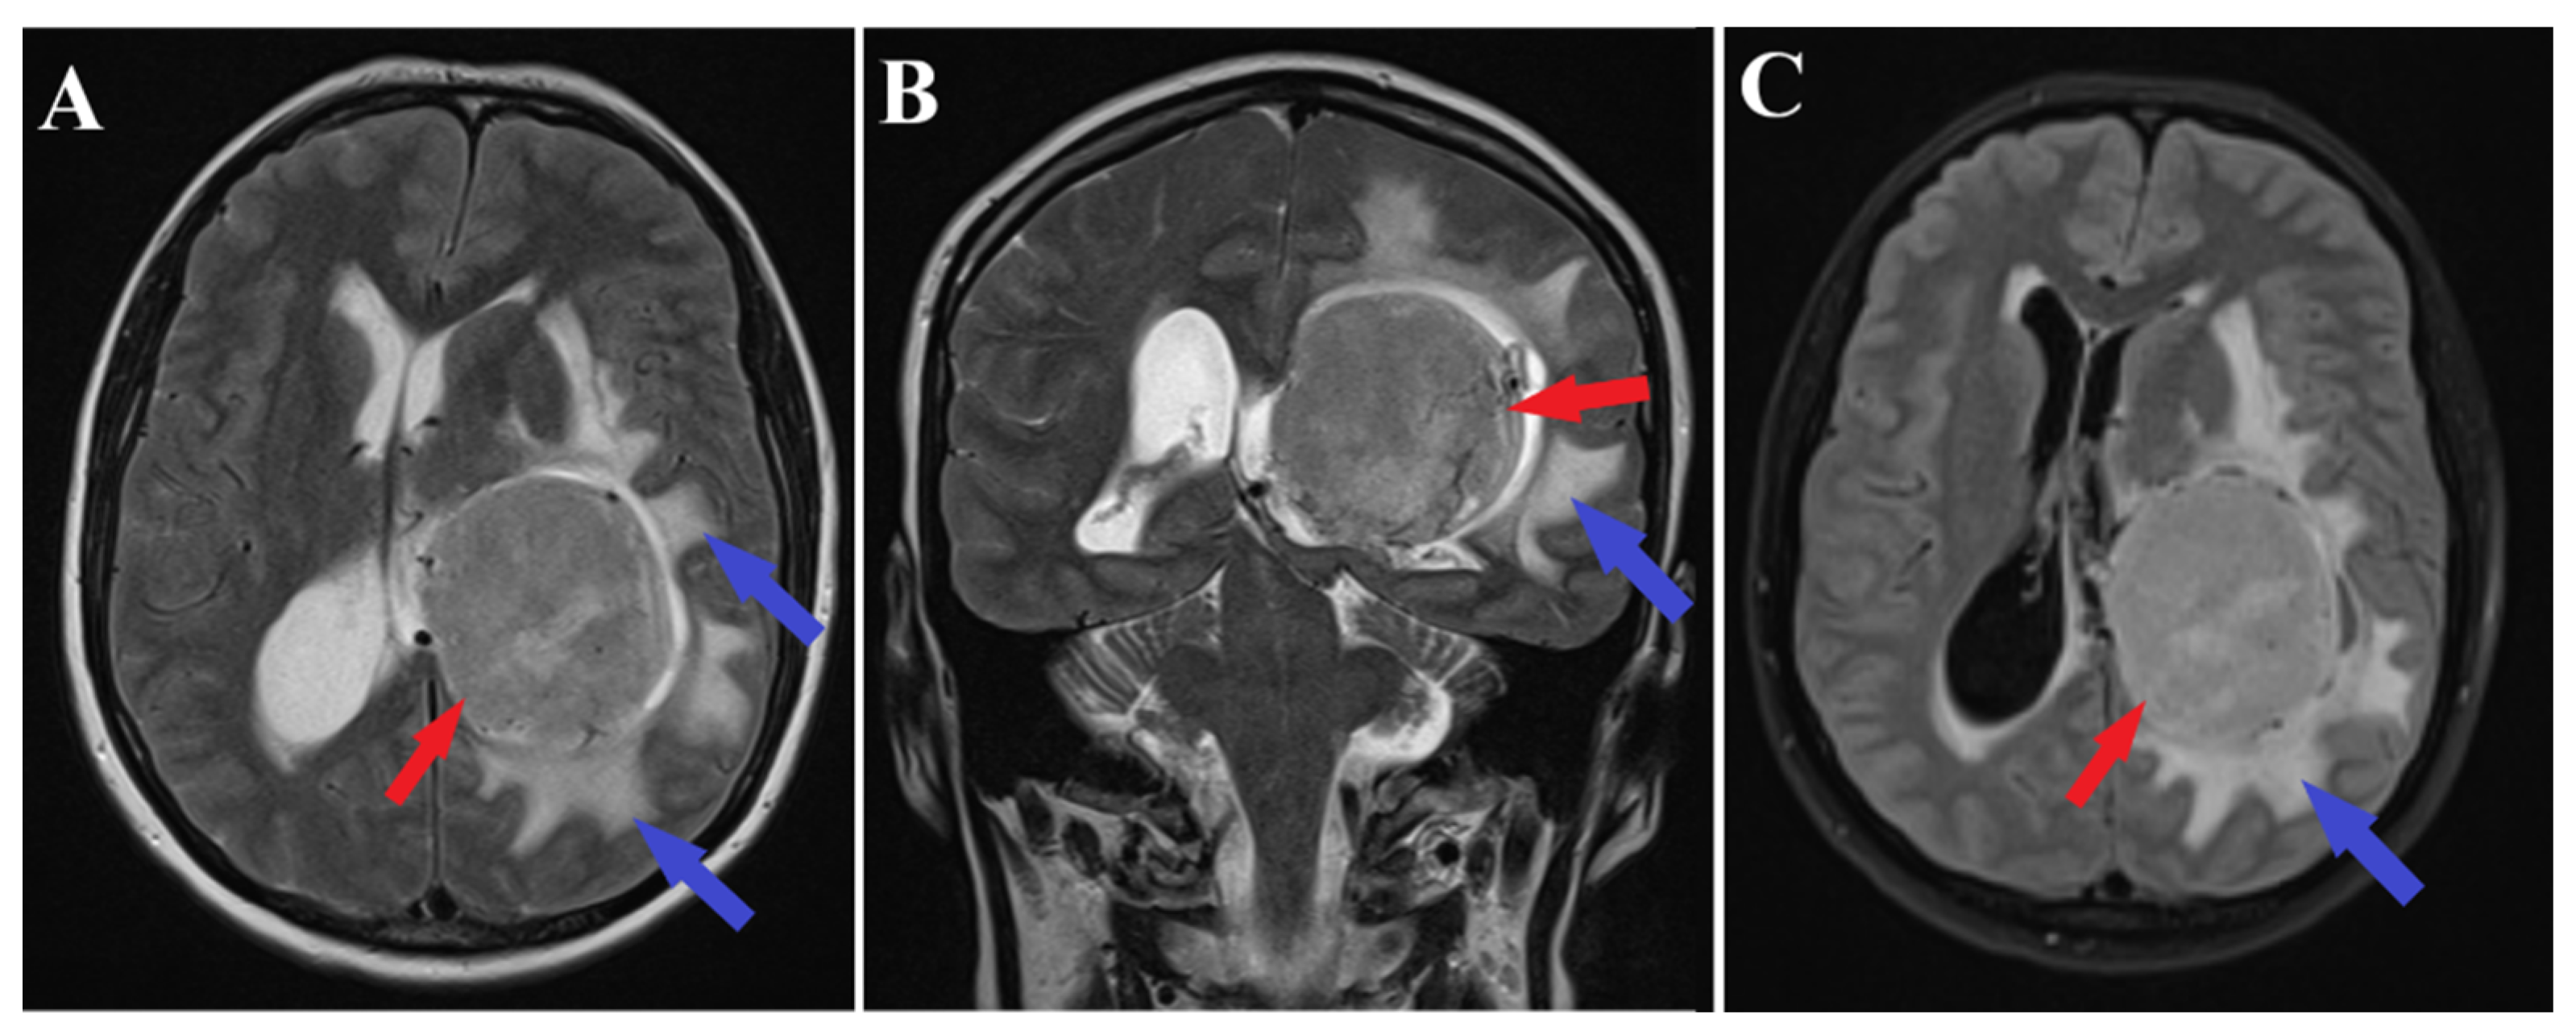

Follow-up evaluations at 3 months and 1 year post-surgery revealed mild, predominantly expressive mixed aphasia. Non-contrast CT scans identified a region of hypodensity in the left temporo-parietal area, indicative of post-surgical changes without any mass effect or contrast uptake, suggesting a sequela. No evidence of tumor recurrence or residual meningioma was observed (Figure 5). Throughout the follow-up period, the patient was maintained on antiepileptic medication, with no reported episodes of seizures.

Figure 5.

Follow-up CT scans. 3 months follow-up CT scan (A) and 1 year follow-up CT scan (B) demonstrate successful complete resection of the meningioma (red arrows) without residual tumor fragments.